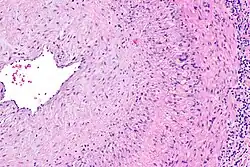

The gold standard for diagnosing temporal arteritis is biopsy, which involves removing a small part of the vessel under local anesthesia and examining it microscopically for giant cells infiltrating the tissue.[23] However, a negative result does not definitively rule out the diagnosis; since the blood vessels are involved in a patchy pattern, there may be unaffected areas on the vessel and the biopsy might have been taken from these parts. Unilateral biopsy of a 1.5–3 cm length is 85–90% sensitive (1 cm is the minimum).[24] Characterised as intimal hyperplasia and medial granulomatous inflammation with elastic lamina fragmentation with a CD4+ predominant T cell infiltrate, currently biopsy is only considered confirmatory for the clinical diagnosis, or one of the diagnostic criteria.[11]